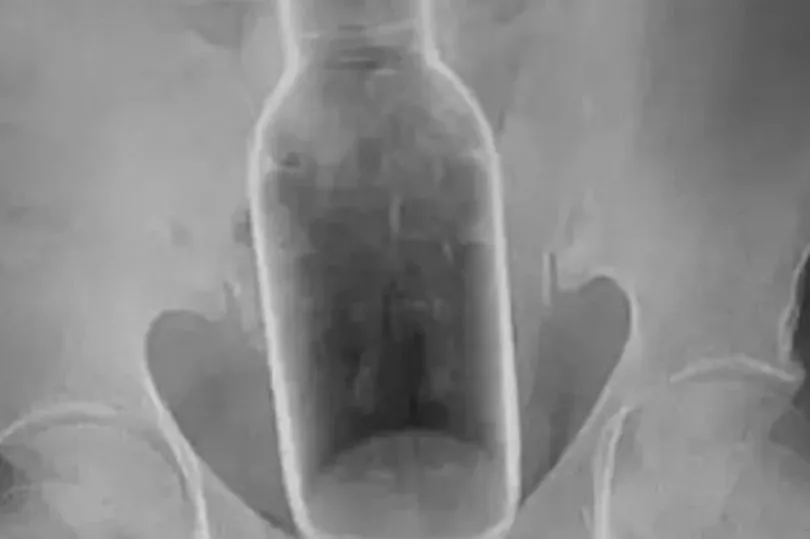

„A röntgenfelvételen jól látszott, hogy az egész üveg felcsúszott a páciens végbelébe. Képzeljék csak el, egy 17 centis üveg! Nem csoda, hogy majdnem elájult a fájdalomtól” – mondta megdöbbenten az orvos.